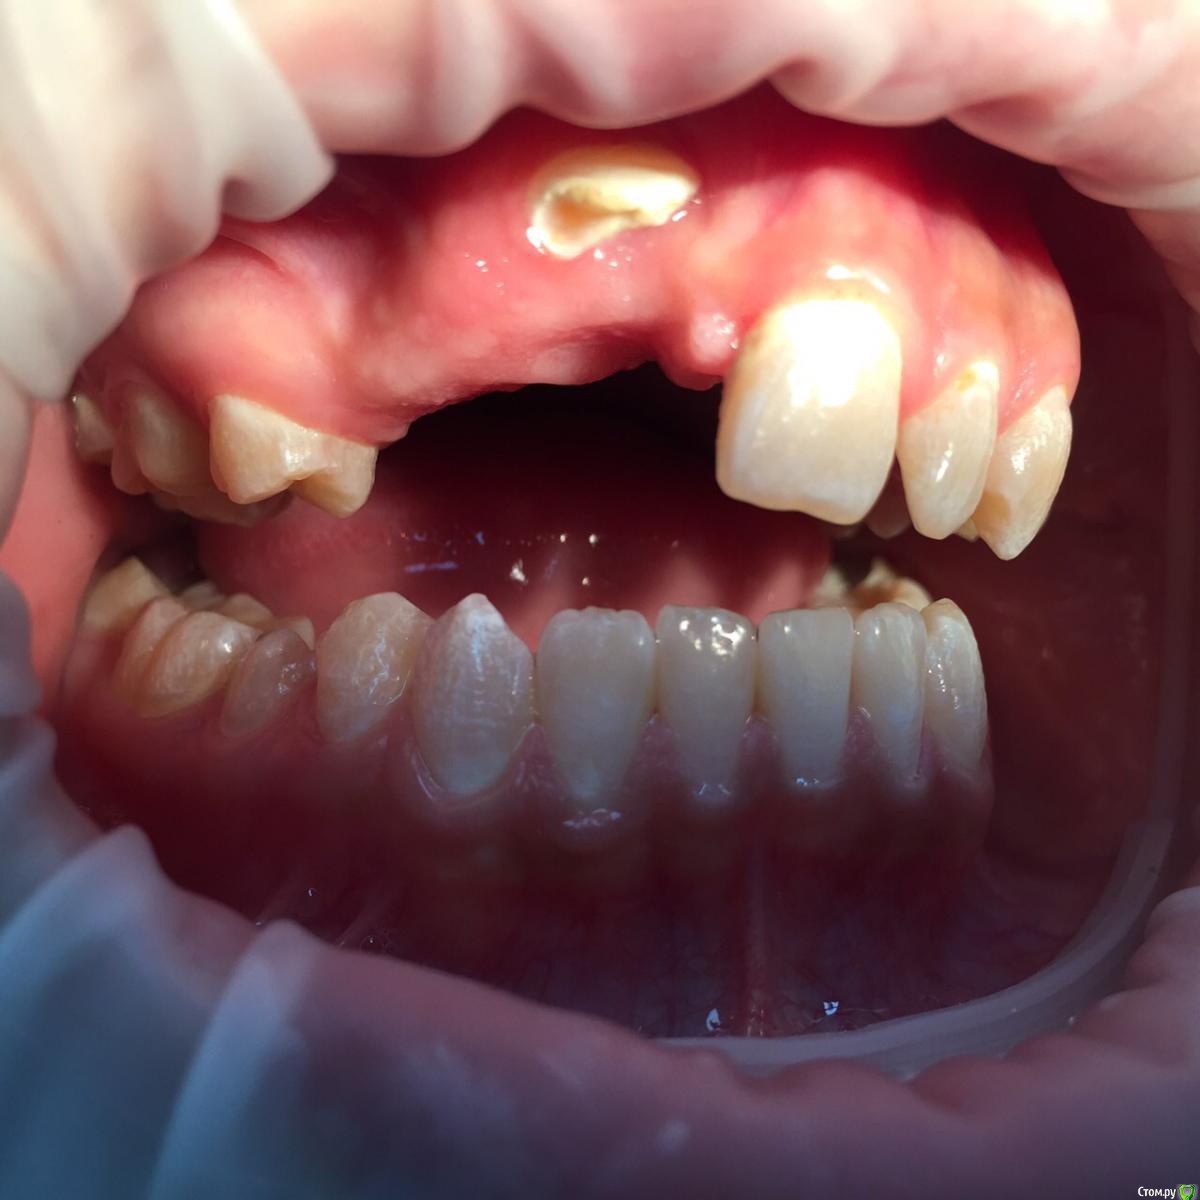

Солнечный СВЕТ Опубликовано 15 февраля, 2015 Поделиться Опубликовано 15 февраля, 2015 Девочка 14 лет, зубы не прорезались,у девочки уже комплекс,родители тоже не знают что делать,готовы ехать в другой город только бы помог кто нибудь,сейчас носит чсп,какие возможны варианты лечения и куда можно обратиться чтобы смогли помочь?!?!?!?! Ссылка на комментарий

SDC Опубликовано 15 февраля, 2015 Поделиться Опубликовано 15 февраля, 2015 (изменено) А почему не начато ортолечение с вытяжением не прорезавшихся?Наша ортодонт несколько кейсов с непрорезавшимися клыками-премолярами сейчас ведет и как то обыденно все проходит. Изменено 15 февраля, 2015 пользователем SDC Ссылка на комментарий

SDC Опубликовано 15 февраля, 2015 Поделиться Опубликовано 15 февраля, 2015 (изменено) Ориентировочный план: 1-е посещение : консультация с КТ и слепками (принятие решения о том в какой последовательности вытягивать зубы) скорее всего, возможно по моделям и КТ без пациентки. 2-е посещение: начало лечения, будет начинаться с раскрытия и диагностического вытягивания ретинированных зубов (последовательность будет ясна после диагностики КТ). Аппарат для диагностического вытягивания: скорее всего кантилевер. В среднем плановые визиты на 1м этапе : 1-е с периодичностью в 1,5-2 месяца. После положительной динамики выдвижения ретинированных зубов, переход на полную брекет-систему. Изменено 15 февраля, 2015 пользователем SDC Ссылка на комментарий

krokomot Опубликовано 28 февраля, 2015 Поделиться Опубликовано 28 февраля, 2015 (изменено) ничего подобно не произойдет если все делать правильно, но возможно, что головоломка и не сложится, хотя складывались и не такиеобязательно :наладить гигиену,сделать модели и ктфиксация системывытяжениеПорядок время и последовательность определяться после изучения кт и моделей. Изменено 28 февраля, 2015 пользователем krokomot 1 Ссылка на комментарий